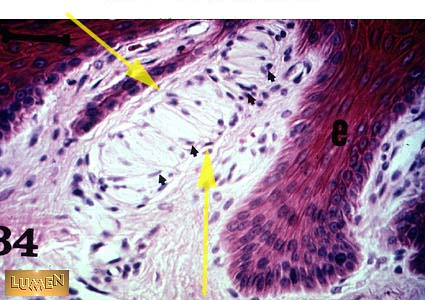

Meissners corpuscle